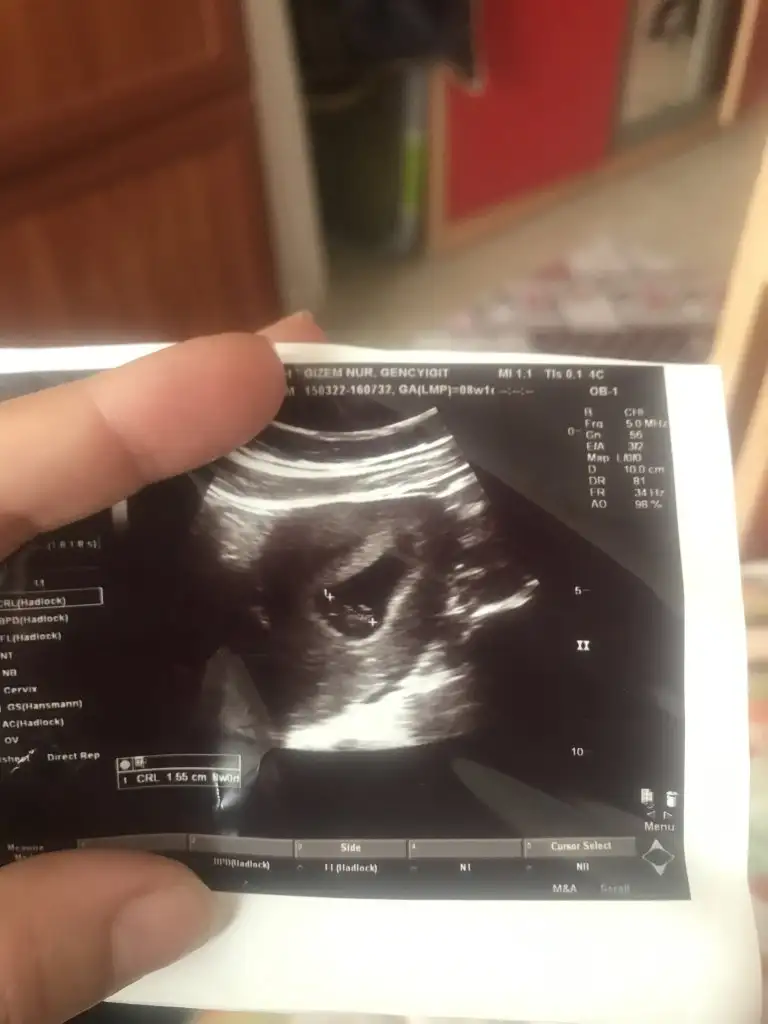

kuzum bence kız8+1 karından usgacaba ne

Gizemcim erkek gibi duruyor kaçıncı hafta fotosu?Karın usgsi çok merak ettim